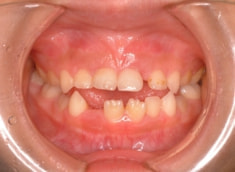

治療後(1年5ヶ月後)